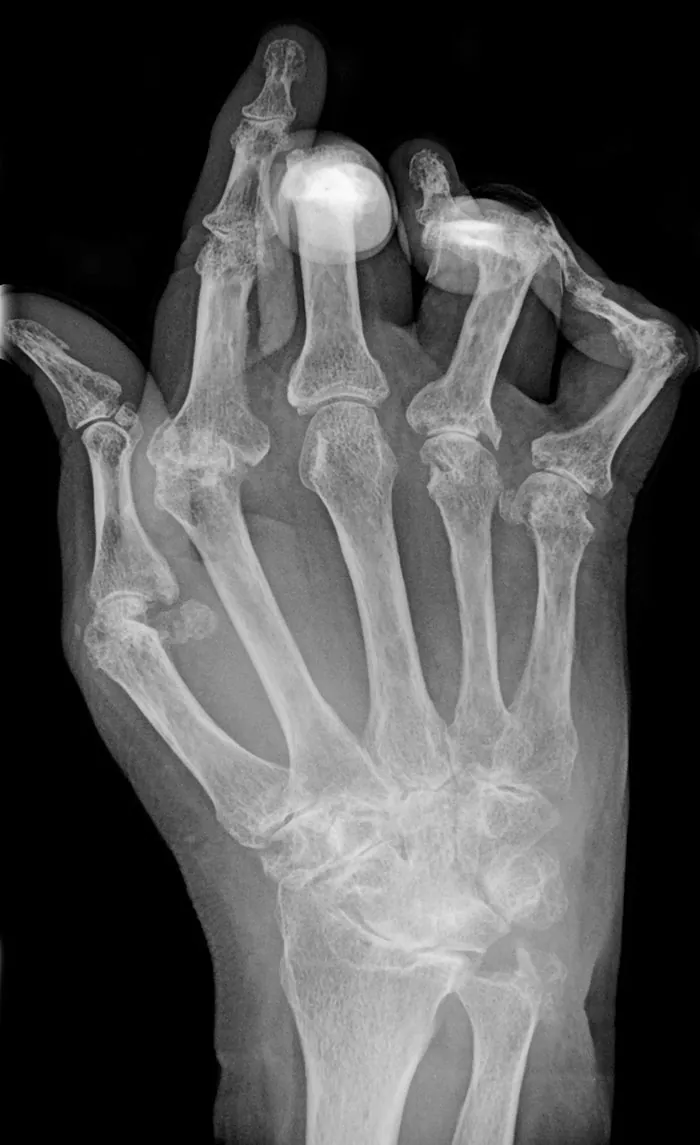

The functional status is a measurement of a patient’s ability to perform physical movements (e.g., walking, standing) and higher-level activities (e.g., activities of daily living, filling occupational and societal roles). An impairment or decline in functional status can impede daily routines, self-care, and autonomy. These impairments can be caused by disease (Figure 9.2), deconditioning, environmental changes, a shift in social supports, or advanced age.

X-ray showing rheumatoid arthritis in a hand

Figure 9.2 This patient has rheumatoid arthritis and has developed contractures in their hands, making eating, dressing, and toileting difficult to perform independently. (credit: modification of work "RheumatoideArthritisAP.jpg" by Bernd Brägelmann/Wikimedia Commons, CC BY 3.0)